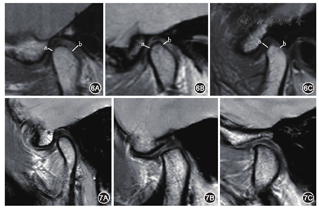

见图11,在张口斜矢状位PDWI图像上,经过关节窝顶部的水平切线a与经过关节结节顶部的垂直线b相交与O点,从O点顺时针开始按0~90°、90~120°、>120°分为3个区,其中关节窝顶部切线位于0°,关节结节垂直线位于90°。髁突头部位于0~90°区间内为运动受限;髁突头部位于90~120°区间内为正常;髁突头部位于>120°区间内为运动过度[16]。